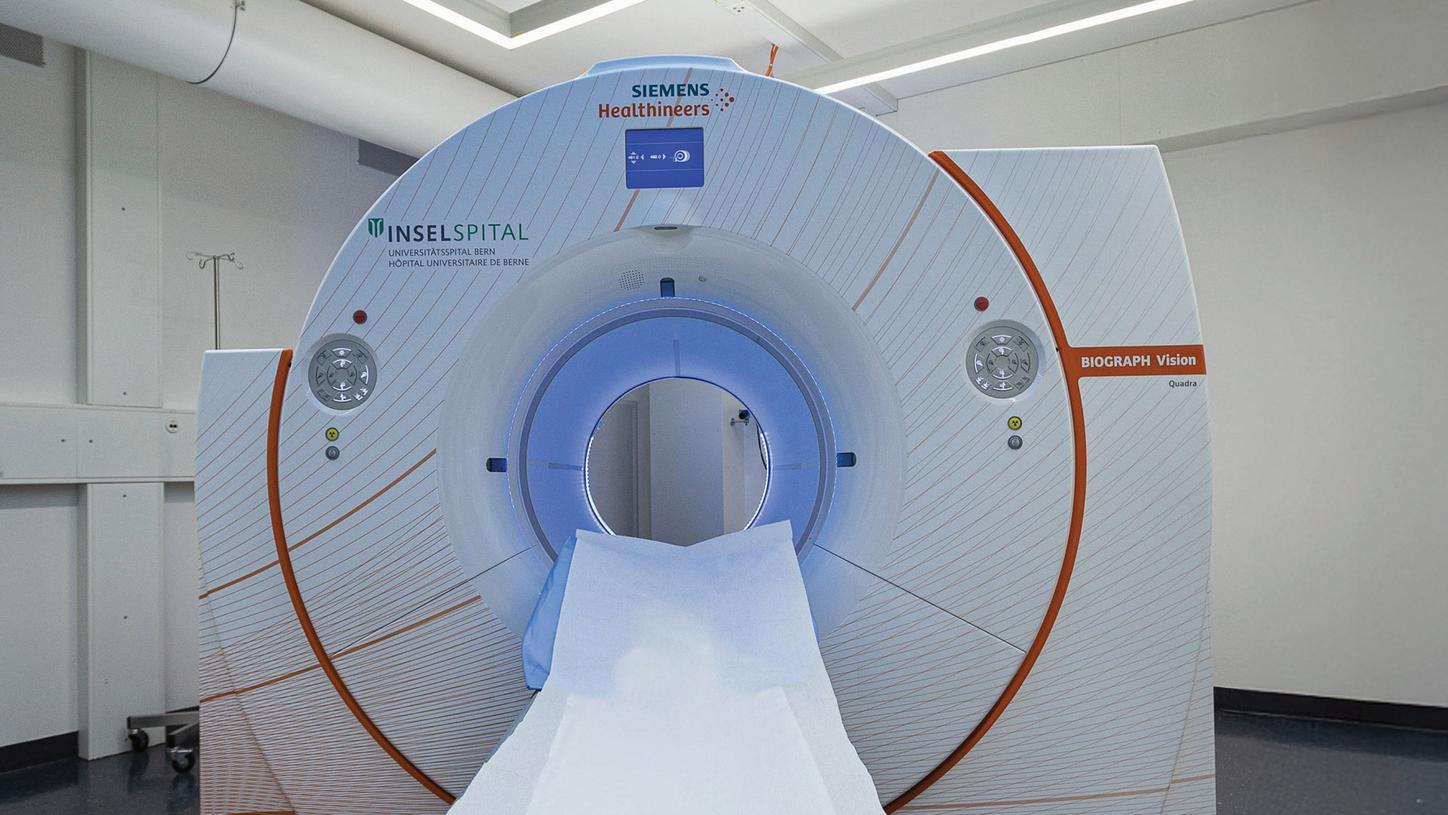

Answering to clinical needs in oncology, neurology, cardiology, and radiology, Siemens Healthineers Molecular Imaging systems provide PET/CT, SPECT, and hybrid SPECT scanner (SPECT/CT) solutions to help clinicians diagnose, treat, and monitor diseases more confidently.